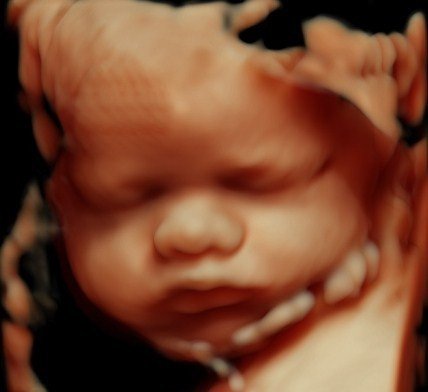

View beautiful baby scan images captured in our studios

Baby scan image 3